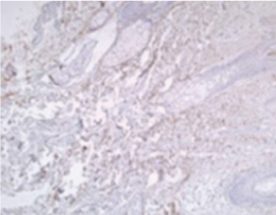

ทำหน้าที่โดยตรงกับไฟโบรบาสต์ ( fibroblasts ) ในชั้นหนังแท้

โดยสัมผัสโดยตรงกับเซลล์เส้นใยเพื่อกระตุ้นส่วนประกอบต่าง ๆ และสร้างเอลาสตินเพื่อช่วยรักษาาความยืดหยุ่นและความหนาของผิว

โปรติโอไกลแคน ( proteoglycan ) เพื่อช่วยเพิ่มความแข็งแรงและเพิ่มความชุ่มชื้น ปรับปรุงโครงสร้างของผิวหนัง

สร้างหลอดเลือดใหม่ ปรับปรุงการไหลเวียนของเลือด และปรับการบำรุงผิว